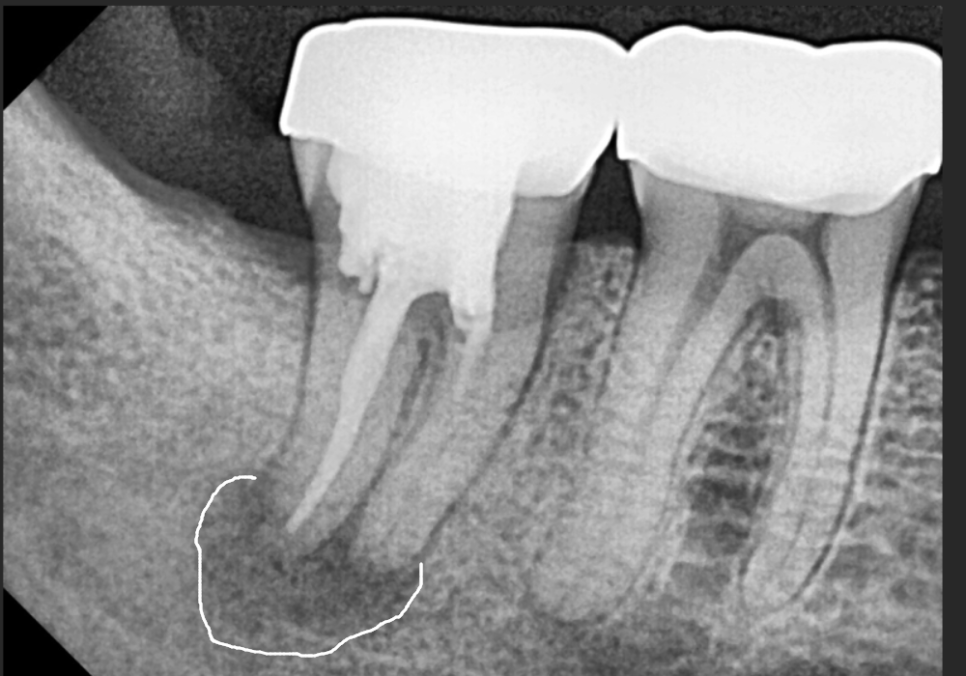

3D CT를 볼까요?

빨갛게 표시한 부분은

아래턱의 감각을 담당하는 주요 신경인

하치조 신경이고,

노란색 부위가 염증으로 인해

뼈가 녹아버린 공간이에요.

임플란트를 심을 때 가장 중요한 것은

이 신경을 피해 안정적으로 식립하는 것인데요.

이 상태에서 바로 심게 되면

뼈가 녹아 텅 빈 공간에 임플란트 뿌리가

제대로 고정될 수 없겠죠~

또한 임플란트가 지지력을 얻으려면

최소 7~8mm의 뼈 길이가 확보되어야 하는데,,

사진을 보면 뼈가 녹은 지점부터

신경까지의 거리가 거의 닿을 듯 가깝습니다.

이런 경우 무리하게 바로 심다가는

자칫 신경을 건드릴 위험이 커요.